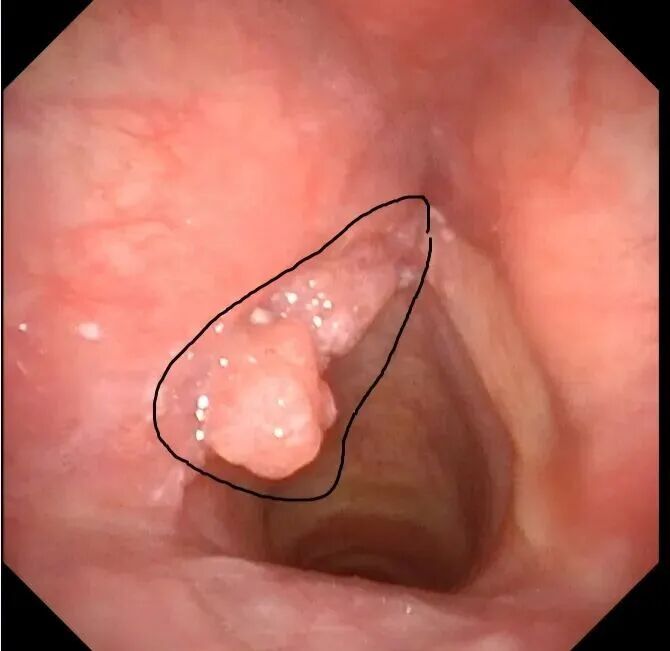

喉镜检查,黑圈位置为病变组织

喉镜检查提示:左侧声带异常新生物,形态高度疑似恶性肿瘤。后续病理活检证实为鳞状细胞癌,病变范围较大,累及甲状软骨内膜,属喉恶性肿瘤中晚期。所幸目前未发现明确转移迹象,最终确诊为喉恶性肿瘤(声门型,鳞状细胞癌,T3N0M0,III期)。